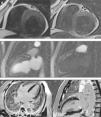

(A) Short‐axis T2‐weighted images with multiple unexpected small vascular structures in the anterior and posterior interventricular grooves; (B) first‐pass myocardial rest perfusion imaging in 2‐chamber view, showing epicardial hyperenhancement of the anterior wall simultaneous with aortic opacification (left) and earlier perfusion of the mid and apical anterior segments (right); (C) subendocardial late gadolinium enhancement in the apical inferior myocardial segment, in 4‐chamber and 2‐chamber views.